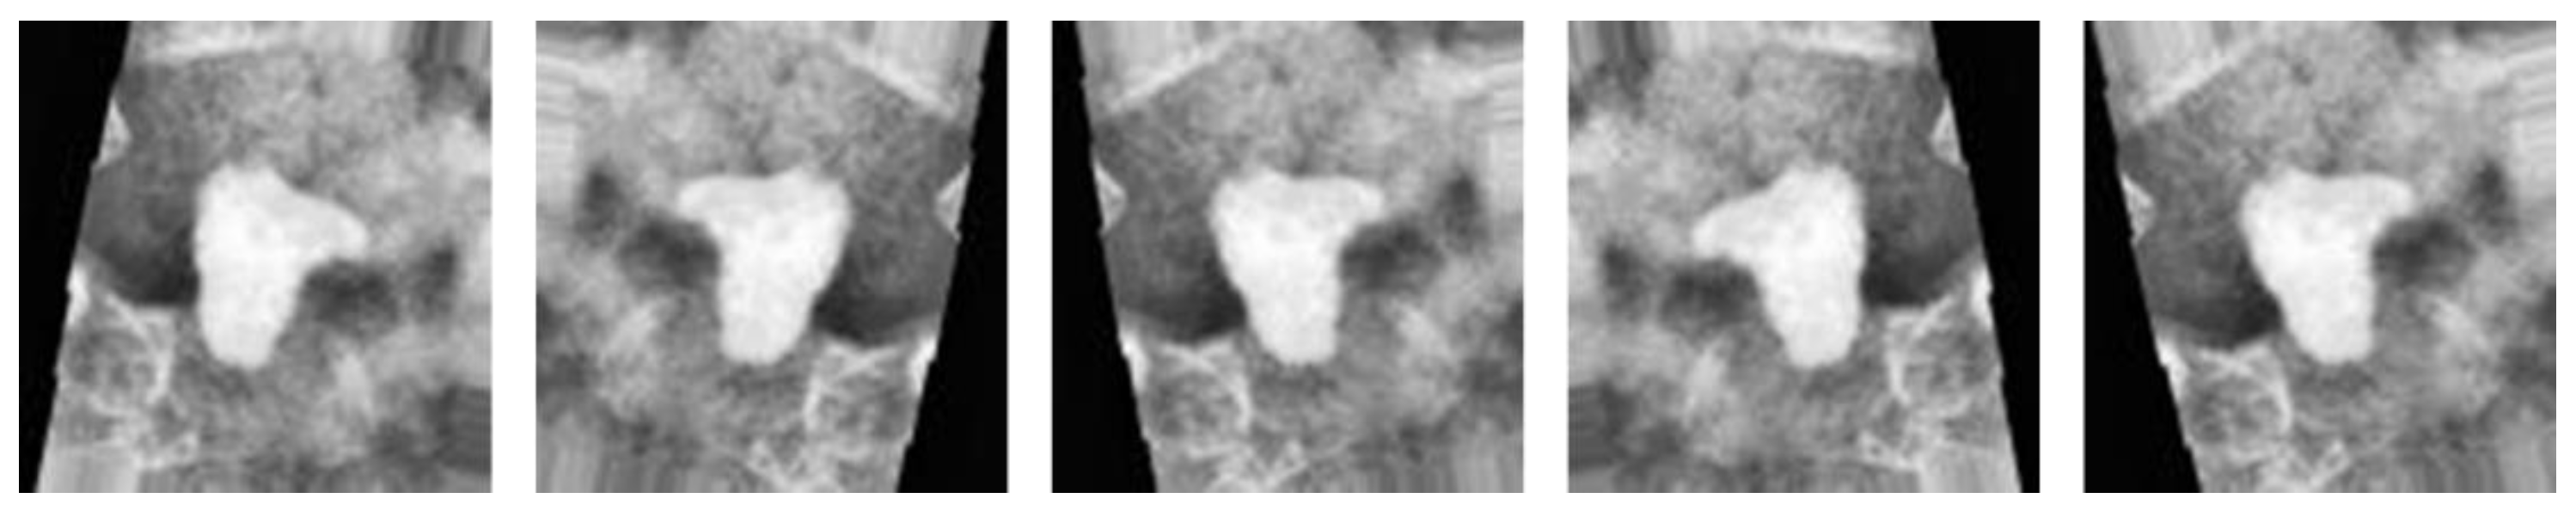

3.4. Subsystem 2—Segmentation Model for Medical Images

4. Discussion